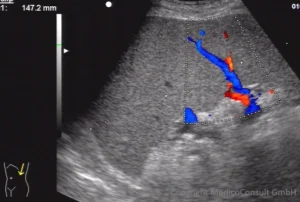

Splenomegalie

![]() Erhebliche Vergrößerung der Milz. Der untere Milzpol überragt die linke Niere deutlich. Zusammen mit einer unauffälligen Leber und einem auffälligen Blutbild ist die Indikation zu einer weiteren hämatologischen Abklärung gegeben: beispielsweise Lymphomkrankheit, Osteomyelofibrose? |